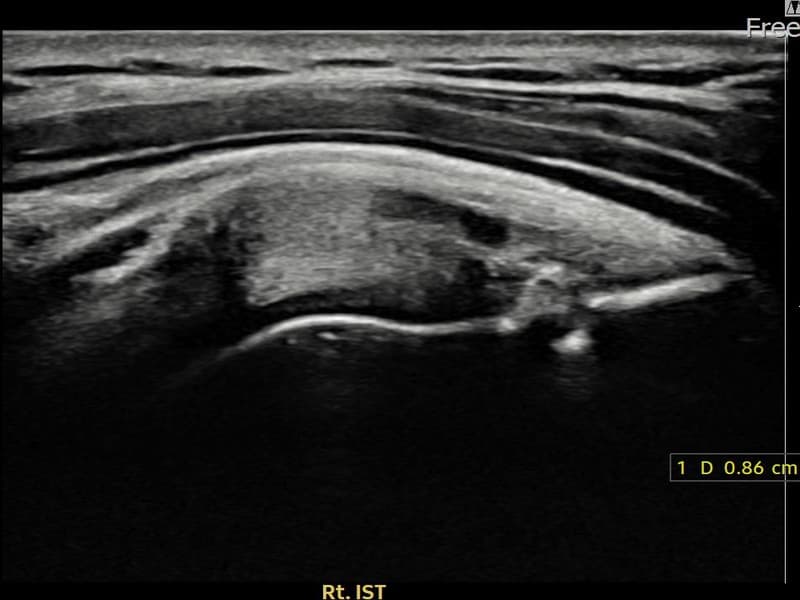

시술 전 초음파 측정 결과 파열 크기는 8.6mm × 4mm (힘줄 두께의 약 45% 결손)로 확인되었습니다. 시술 전 초음파에서 우측 극하근건 부착부의 에코 단절과 힘줄 결손 소견이 확인되었으며, 파열 크기는 8.6mm로 측정되었습니다. 시술 후 초음파에서 부착부 연속성이 회복되고 결손 부위에 재생 조직이 형성된 것이 관찰되었습니다.

30대 후반 남성 환자분으로, 헬스 및 수영을 즐기시다가 우측 어깨 후방 통증이 생겨 내원하셨습니다. 운동 중 어깨에 과도한 외회전 부하가 반복되어 극하근건이 손상된 것으로 판단되었습니다. 초음파 검사에서 극하근건 부착부 부분파열이 확인되었고, 파열 크기는 8.6mm로 의미 있는 손상이었습니다. 수술 없이 초음파 유도 하 축소봉합술을 시행하였으며, 시술 후 보조기 착용 6주와 단계적 재활 운동을 통해 회복을 진행하였습니다. 시술 11주 후 추적 초음파에서 부착부 힘줄 연속성이 회복되어 운동 활동에 복귀하셨습니다.